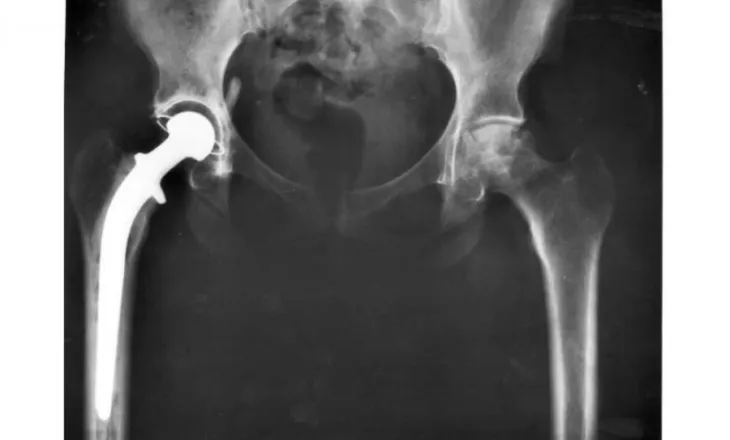

Protezat moderne të legenit kanë pothuajse dyfish më shumë gjasa se modelet e vjetra të zgjasin të paktën 25 vjet, sipas një studimi të publikuar në The Lancet. Studiuesit, përmes një rishikimi të gjerë dhe analize statistikore, vlerësojnë se 92% e protezave moderne mund të funksionojnë për të paktën 25 vjet. Ky është një përmirësim i madh krahasuar me studimet e mëparshme mbi teknologjitë e vjetra, ku vetëm rreth 58% e protezave arrinin 25 vite përdorimi. Ndërrimi i legenit është një ndërhyrje shumë e suksesshme që ndihmon miliona njerëz në mbarë botën të rikthejnë lëvizshmërinë dhe të përmirësojnë cilësinë e jetës. Meqë gjithnjë e më shumë pacientë të rinj i nënshtrohen kësaj procedure dhe jetëgjatësia po rritet, është e rëndësishme të dihet sa zgjasin këto...